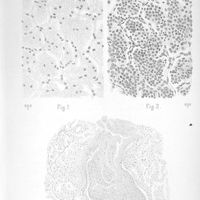

0033 - Page sans numérotation - [Planches]0033 - Page sans numérotation - [Planches]

0041 - Page sans numérotation - [Planches]0041 - Page sans numérotation - [Planches]

0043 - Page sans numérotation - [Planches]0043 - Page sans numérotation - [Planches]